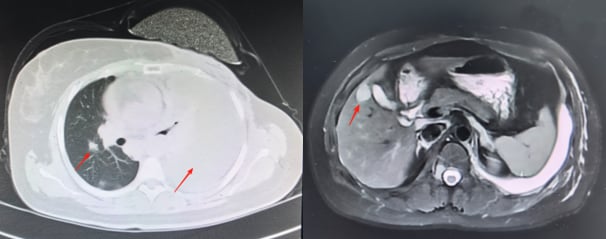

患者接受了规范的初始治疗:手术(左乳单切+SLNB+ALND),辅助化疗(AC-T*8周期),辅助放疗(患侧胸壁+锁骨上下区,50Gy/2Gy/25次),以及内分泌治疗(OFS+来曲唑)。2023年3月,为了强化治疗效果,医生为她加用了阿贝西利进行强化内分泌治疗。然而,尽管进行了积极治疗,疾病的进展依然迅速。2025年1月复查时疾病稳定,但仅两个月后,2025年3月强化内分泌治疗结束后,2025年4月复查就提示肺转移可能。胸部CT、骨扫描、头颅+腰椎CT等影像学检查均显示多发可疑病灶。最终,2025年5月的复查确诊为左乳癌术后肺、肝、左侧胸膜、骨转移,肝脏穿刺病理进一步证实为转移性腺癌,ER表达降至13%中+,PR阴性,HER2(2+),FISH阴性,再次确认HER2低表达。